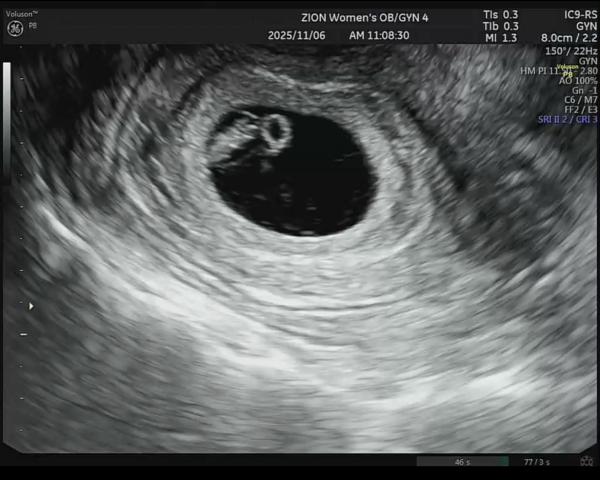

置星焼税 2025鰍 11杉 6析 姶紫

呪尻戚 3析属 何原沿剛 晦艦 背衣